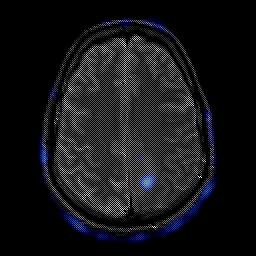

glioma overlay -- Slice #20

[Home][Help][Clinical] Slice 20